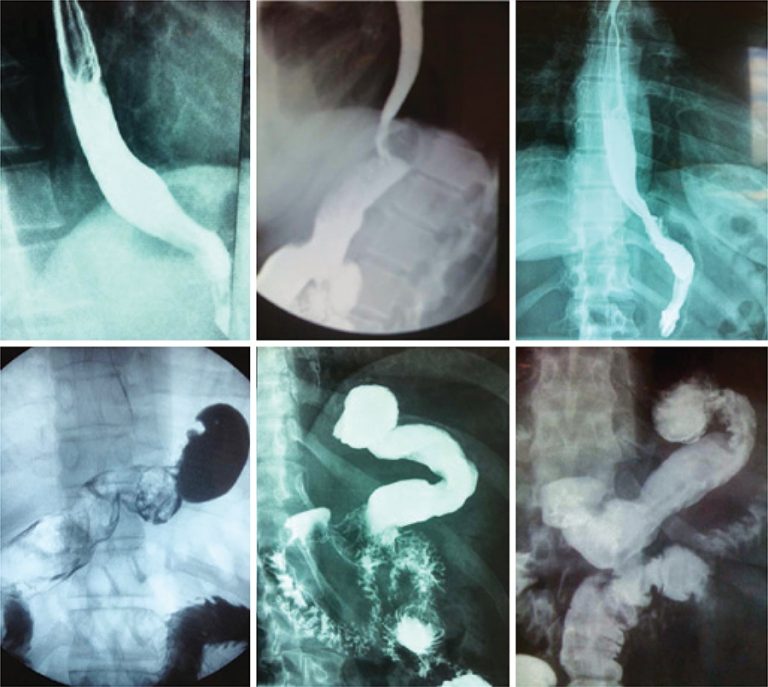

Objective Sleeve gastrectomy is the fastest growing surgical procedure to treat obesity in the world but it may cause or worsen gastroesophageal reflux disease. This article originally aimed to describe the addition of anti-reflux procedures (removal of periesophageal fats pads, hiatoplasty, a small plication and fixation of the gastric remnant in position) to the usual sleeve gastrectomy and to report early and late results. Methods Eighty-eight obese patients that also presented symptoms of gastroesophageal reflux disease were submitted to sleeve […]